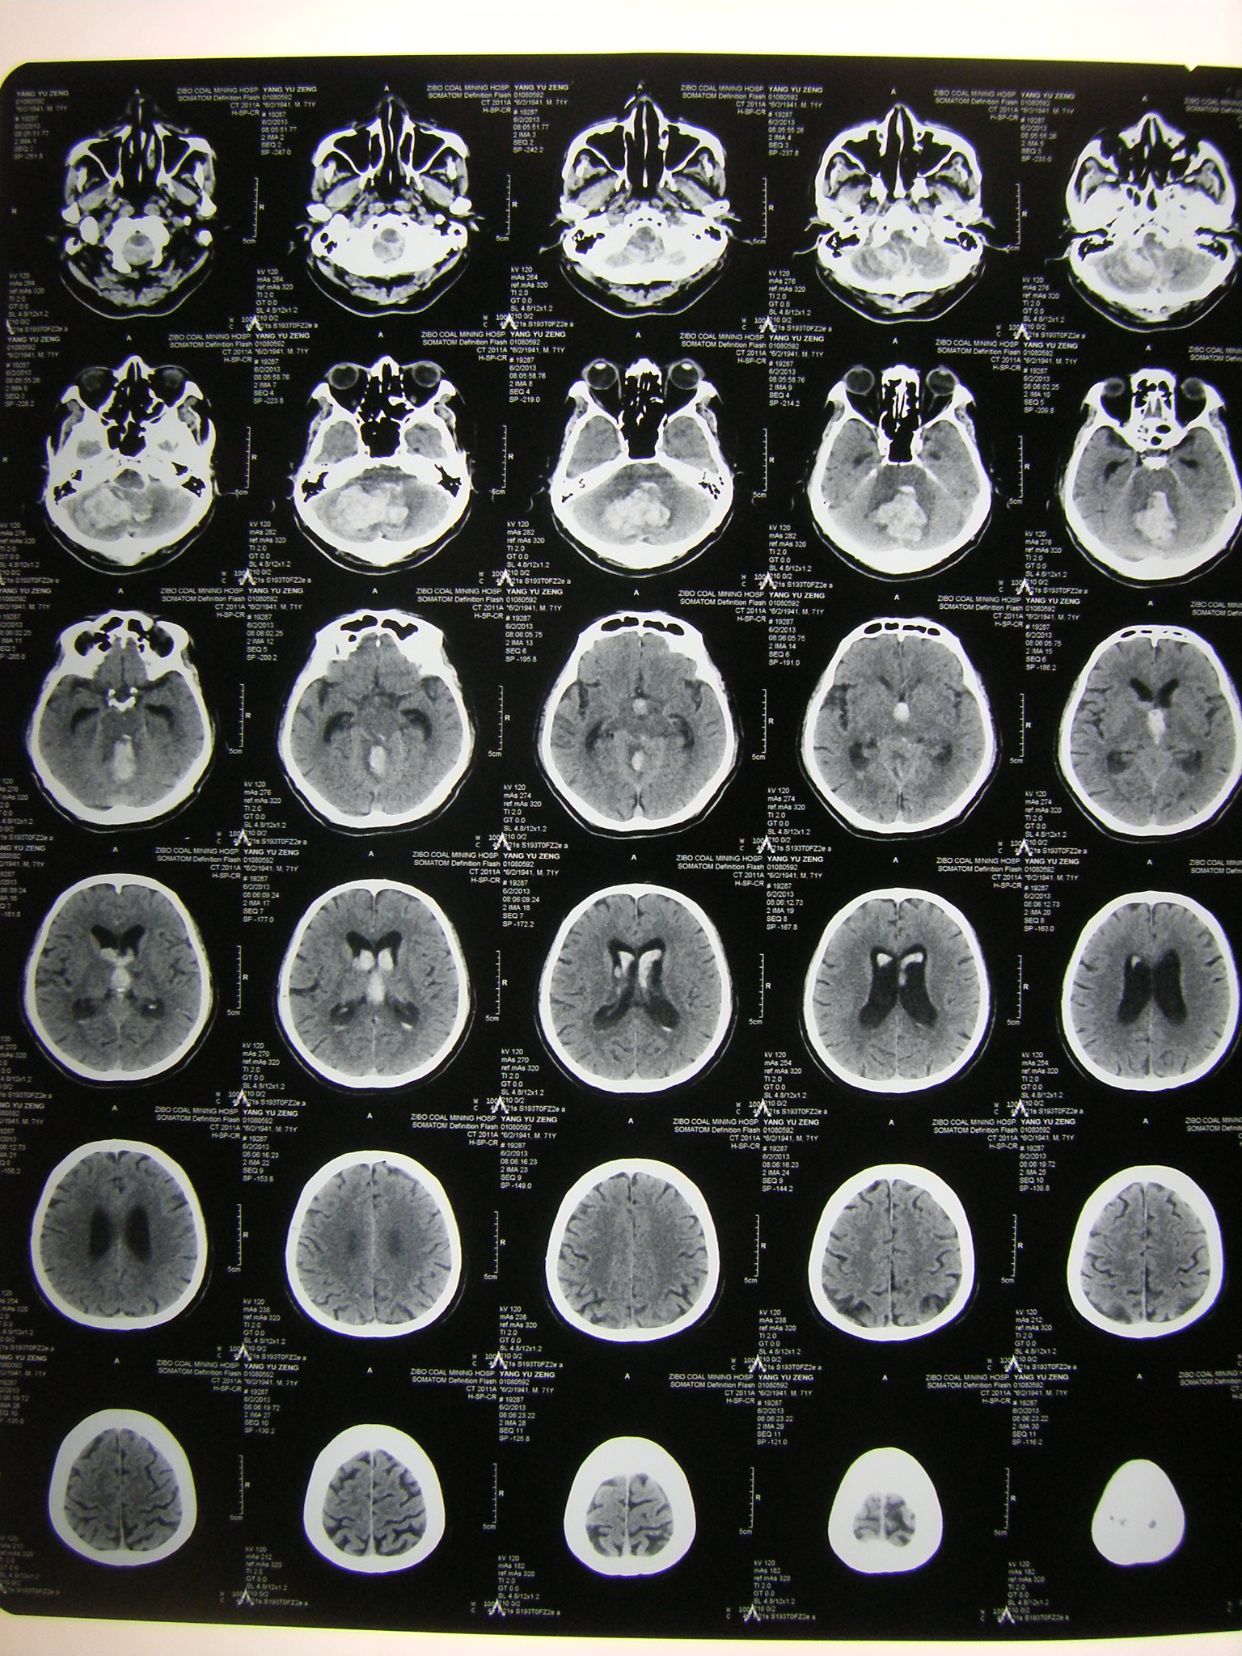

例1,患者男,70岁,突发意识不清1小时入院,有高血压等病史多年,深昏迷状,入院查体时出现呼吸停止,双瞳孔散大,立即气管插管,人工呼吸,建立静脉通道,应用甘露醇等。

CT显示小脑大量出血并破入全脑室,梗阻性脑积水,脑干受压变形,与家属沟通并签字后,急症行脑室引流术,后颅凹开颅血肿清除术,气管切开术。

术后3天CT复查示,血肿清除满意,基底池四脑室可见。

术后四周CT复查,脑沟回清楚,无脑积水征象,患者神志清,四肢可遵嘱动作,出院康复。